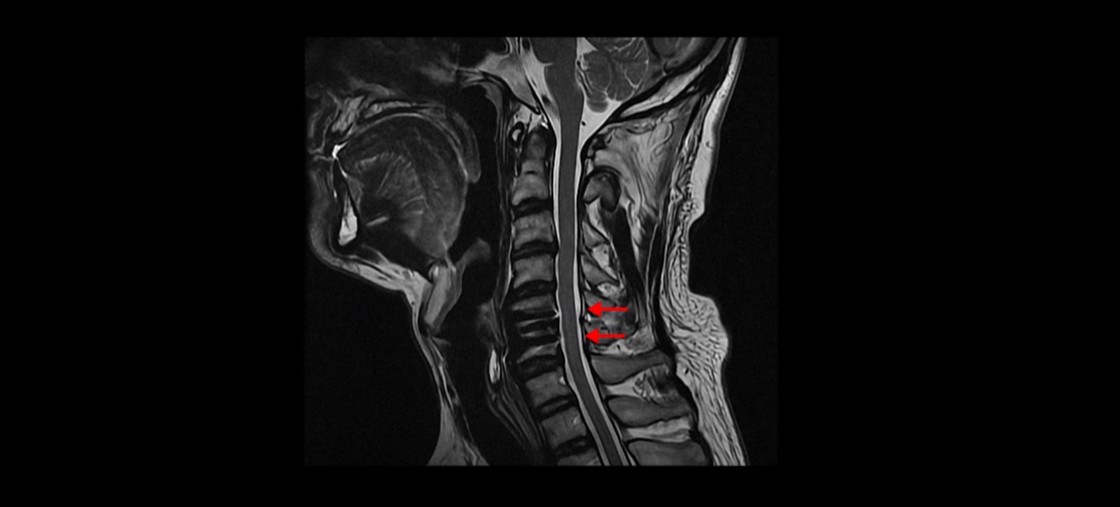

MRI를 보시면 목 5번 6번 마디에 나사가 박힌 유합술이 되어있습니다.

제자리에 나사가 잘 박혀 있고 유합술은 크게 문제가 없는 것으로 보입니다.

수술한 병원에서도 수술은 잘 됐다고 하는데, 문제는 이 환자분이 수술 후에도 엄청난 통증에 시달린다는 겁니다.

저희 모커리한방병원에서는 목이든 허리든 수술이 잘 됐다는 데도 계속 아프다면 당연히 근육 문제를 의심하고 치료해야 한다고 그렇게 반복해서 설명하는데도 신경 주사만 맞거나 아니면 치료를 포기하거나 아니면 추가적인 수술을 받는 분들도 있습니다. 이 환자분도 보시다시피 목의 다른 마디에도 퇴행성디스크와 협착이 있습니다.